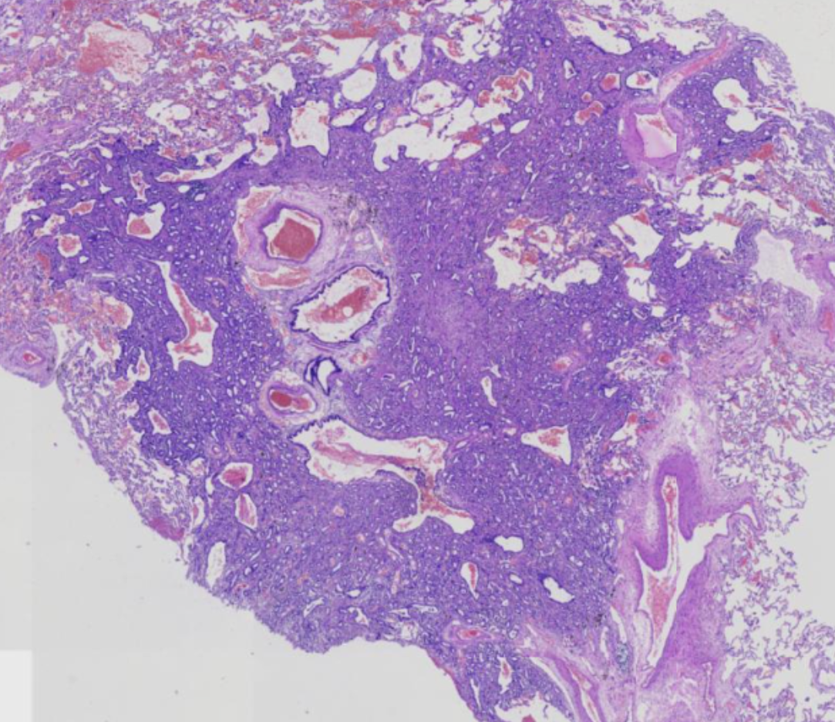

大体检查:

(右上肺结节)部分肺组织一块,大小7.6cm×3.0cm×1.5cm,一侧见一缝合口,长7.6cm,距缝合口2.2cm处见一剖口,切面紧靠胸膜见一灰白色区域,范围0.7cm×0.5cm,界限欠清,质中,余切面,灰红色,质软